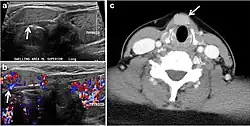

Fig. 4. A 45-year-old male patient presented with anterior mediastinal metastatic PTC lesions and occult primary on imaging. Histopathology examination of the resected thyroid gland revealed micro-foci of PTC; the largest, in the isthmus, measured 4 mm. a transverse greyscale ultrasound of the thyroid demonstrates homogeneous gland with normal echogenicity and size. No focal lesion or micro-calcifications. b Non-enhanced CT scan obtained as part of PET/CT examination shows a heterogeneous, large, relatively dense anterior mediastinal mass (white arrow) with peripheral calcification (arrowheads). Thyroid gland has normal CT appearance with no abnormal FDG uptake (not shown).[1] -

Fig. 7. A 51-year-old female patient post total thyroidectomy for PTC with elevated thyroglobulin measurement. an Axial non-enhanced CT scan of the neck at the level of the thyroid bed demonstrates a well-defined, rounded, homogenously dense soft tissue situated between the trachea and left internal jugular vein (white arrow). b Transverse ultrasound image of the neck demonstrates a well-defined, homogeneous, hypoechoic soft tissue nodule measuring 6 mm (white arrow) with no detected micro-calcifications. Biopsy showed a predominantly residual normal thyroid tissue with micro-foci of PTC.[1] -

Fig. 8. A 48-year-old male patient post total thyroidectomy with PTC recurrence. a Transverse greyscale ultrasound of the neck demonstrates a left thyroid bed heterogeneous, predominantly hypoechoic irregular lesion with calcifications (white arrow). b A spot image of iodine 123 total body scan of the neck demonstrate a focus of abnormal radiotracer uptake at the left thyroid bed (Black arrows) between the annotated markers. c Enhanced axial CT scan of the neck demonstrates an enhancing large left thyroid bed mass (white arrow) with no calcifications. The lesion exerts a mass effect on the oesophagus (black arrow) and is inseparable from the trachea.[1] -

Fig. 9. A 58-year-old male patient with persistence PTC at thyroid bed with hypervascular nodal metastasis. a–c Transverse greyscale and colour Doppler neck ultrasound demonstrate hypoehoic soft tissue in the left thyroid bed (white arrow in a). There are a heterogeneous enlarged lymph nodes at level 2 and 3 with markedly increased vascularity (white arrow in b and c). d–f Enhanced axial CT images of the neck demonstrate a 2.7 × 1.4 cm hypodense soft tissue lesion anterior to the left carotid sheath (white arrow). There are left-sided enhancing abnormal and enlarged lymph nodes at cervical level 2 and 3 (black arrows).[1]